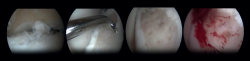

One specific surgical fixation technique is the Lift, Drill, Fill and Fix (LDFF) procedure(45). In this technique, the osteochondral lesion is visualized, and a beaver knife is used to create a flap. The flap is then lifted to allow for debridement and microfracturing of the subchondral bone. Cancellous bone, typically harvested from the distal tibial metaphysis, can be placed in the bed of the flap. Finally, the osteochondral flap is repositioned and fixed using bio-absorbable compression screws, chondral darts or bone pegs.

Fixation techniques have shown clinical and radiological success in 8 out of 10 patients, also maintaining their success in the long term (Figures 5 and 6). As these techniques preserve the hyaline cartilage and provide superior healing of the subchondral bone, they are advantageous over other surgical treatment options for OLTs, when feasible(39,41).